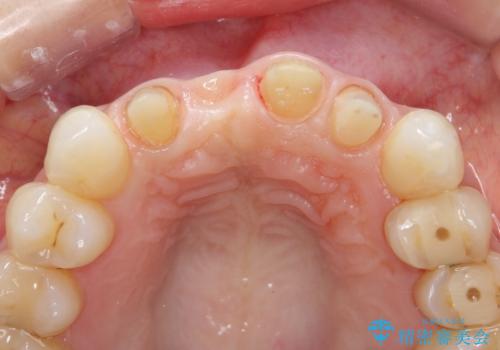

- 前医に前歯の吸収による抜歯の必要性を伝えられ、前歯の審美的な改善・治療を求めて来院されました。

CT撮影を行った結果、右上前歯は吸収が進み抜歯が必要な状態です、

抜歯をせず放置すると、より吸収が進み臨在する歯にも悪影響を及ぼしてしまう可能性が考えられます。

上顎4前歯は、根管治療の既往があり、虫歯も見られたことからブリッジによる治療で審美性の回復を行うとともに臨在歯の虫歯もセラミック治療を行っていきます。